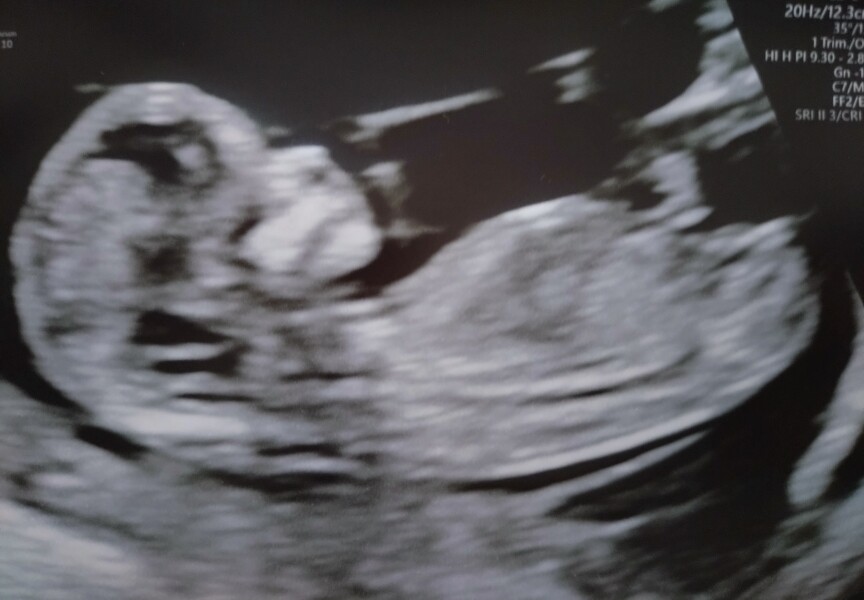

CDD · 23/03/2024 21:49

So had my 12 week scan Thursday went in thinking I was 12+1 but they have dated me at 13+6 so due date is now 27th Sept. Everything was fine they said and we saw a healthy beating heart. Baby was a right wriggler and kept trying to hide. I had my bloods done and was given dates for my consultant appointment, my 2nd NHS scan and the dates for my glucose testing. So happy now finally had my first scan for this pregnancy and feel I can breathe now and try to relax abit more. Hopefully that pregnancy glow starts soon and I get abit of energy back and less sleepy.